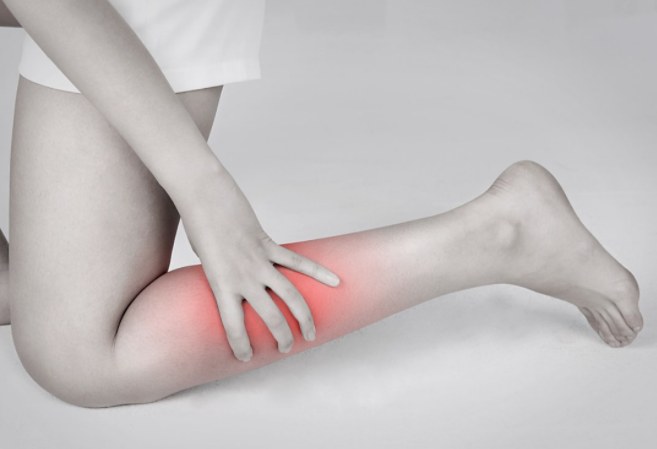

운동을 하거나 평상시 생활을 하다 보면 특정 부위 근육 통증이 느껴지는 것을 볼 수 있습니다. 더 심해진다면 방치하지 말고 진료 및 치료를 받는 것이 좋습니다. 오늘은 그 부위 중에서 흔하게 발생하는 종아리 근육 통증 원인에 대해서 알아보도록 하겠습니다.

우선 종아리 근육 통증이 느껴진다면 가장 먼저 의심해 볼 필요가 있는 것이 바로 종아리 혈액순환 장애입니다. 종아리는 신체 부위 특성상 제일 하단에 위치하고 있어서 혈액순환이 잘 되지 않을 수 있습니다.

혈액순환이 잘 되지 않기 때문에 많이 걷거나 운동을 할 경우에 종아리가 붓거나 통증이 느껴질 수 있습니다. 또한 평소 종아리 근육을 사용하지 않는다면 갑자기 근육통이 올 수 있기 때문에 평소 생활습관이 중요합니다.

종아리 근육 통증 원인 다른 이유는 종아리 근육 파열을 의심해 볼 수 있습니다. 만약 종아리에 무리한 충격을 가하거나 근육이 노화로 인해서 자그마한 충격에도 쉽게 파열될 수 있으니 각별히 주의하시기 바랍니다.